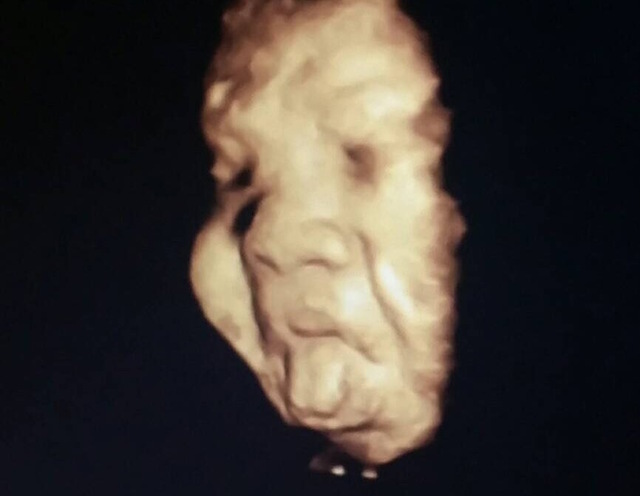

37週0日(37w0d・女の子)|aada1254さん(25歳)

エコー写真撮影時のエピソード:

顔がここまでハッキリと分かるエコー写真は初めてだったので、とても感動的でした。色々な人に見せてあげたい1枚です(^^)

正産期に入り出産も待ち遠しいこの頃なので、実際どんな顔の子が出てくるのか、今から楽しみです!